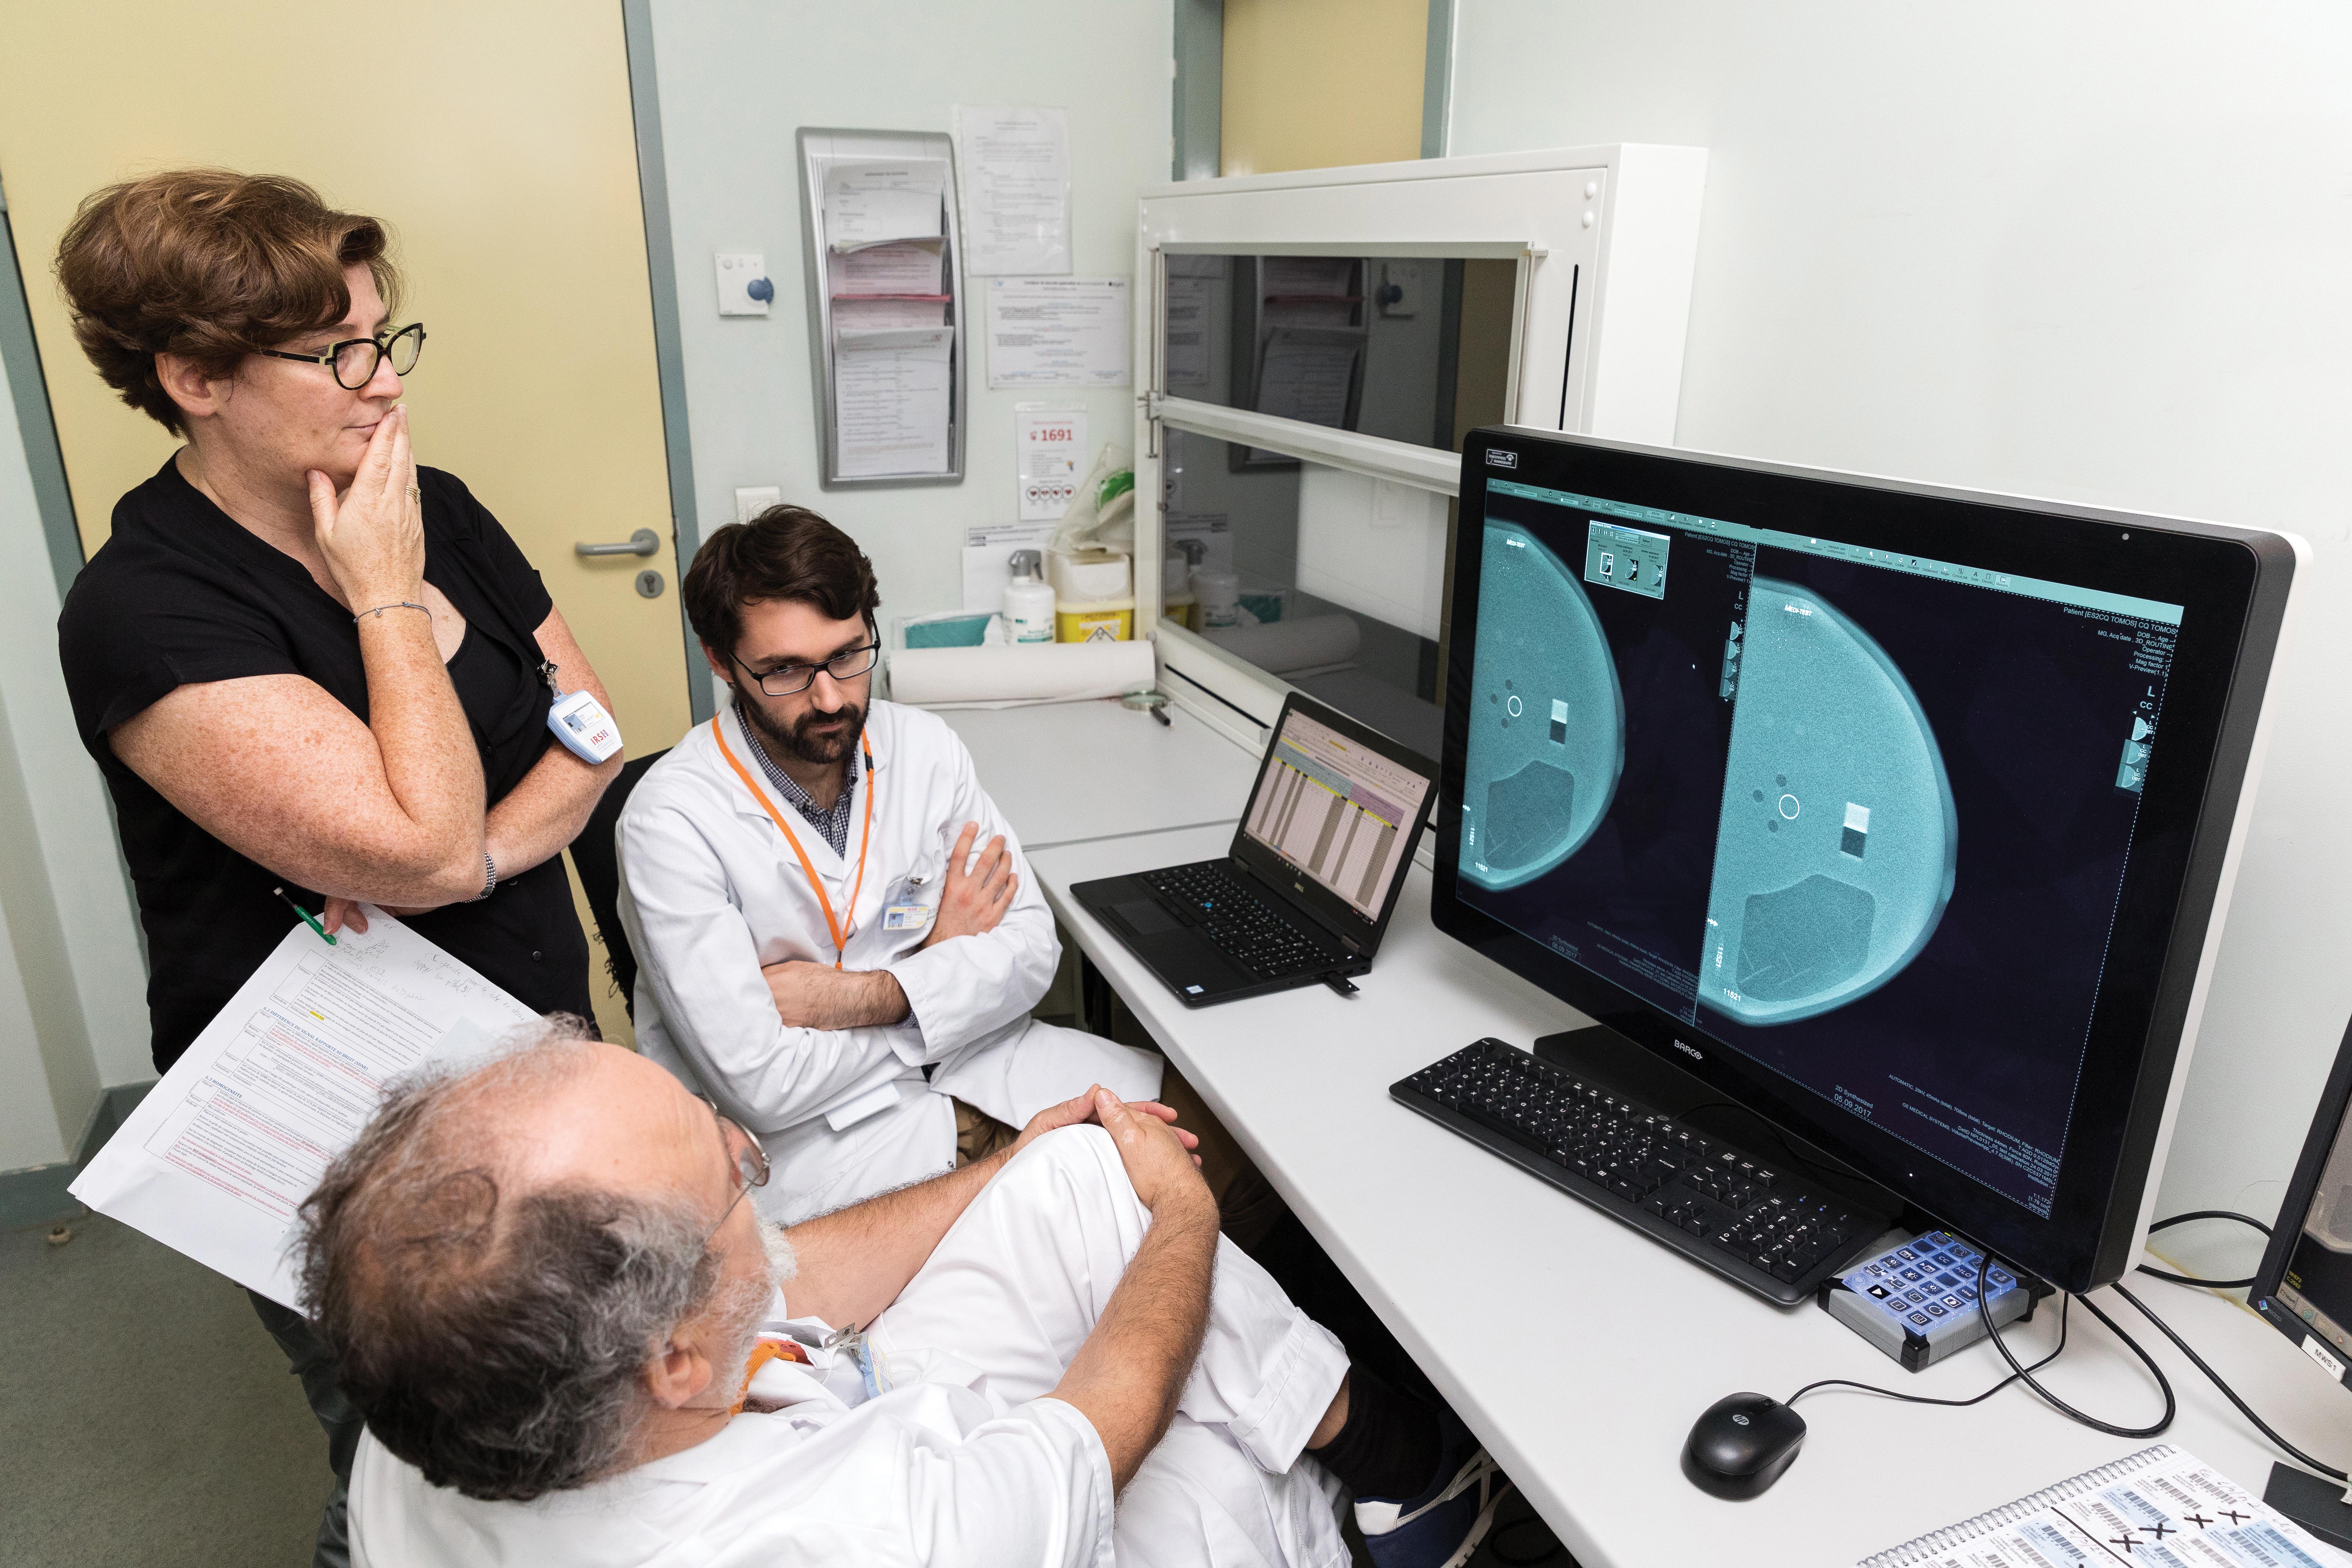

En 2017, l’Autorité de sûreté nucléaire demande à l’Unité d’expertise en radioprotection médicale (UEM) d’étudier la mise en œuvre des IRM-Linac. Ces accélérateurs linéaires sont couplés à l’imagerie par résonance magnétique (IRM). En France, l’Institut Paoli-Calmettes à Marseille (Bouches du -Rhône) est le premier à l’utiliser. Le champ magnétique dû à l’IRM pose question. « Quel est l’impact sur la prise en charge des patients et quel est le contrôle qualité à réaliser ? », Aurélie Isambert, spécialiste en radioprotection médicale, résume les inquiétudes des experts.

L’IRSN forme un groupe de travail avec la Société française de physique médicale (SFPM). En 2017 et 2018, ils auditionnent les fabricants, examinent la littérature et visitent des hôpitaux qui en sont équipés aux Pays-Bas. « Un travail en complémentarité », relate Vincent Marchesi, vice-président de la SFPM. Cette expertise – avis 2018-00232 – compte plusieurs recommandations : ajuster le réglage des accélérateurs à proximité, s’assurer que les physiciens et radiothérapeutes impliqués possèdent des compétences solides en IRM, etc.